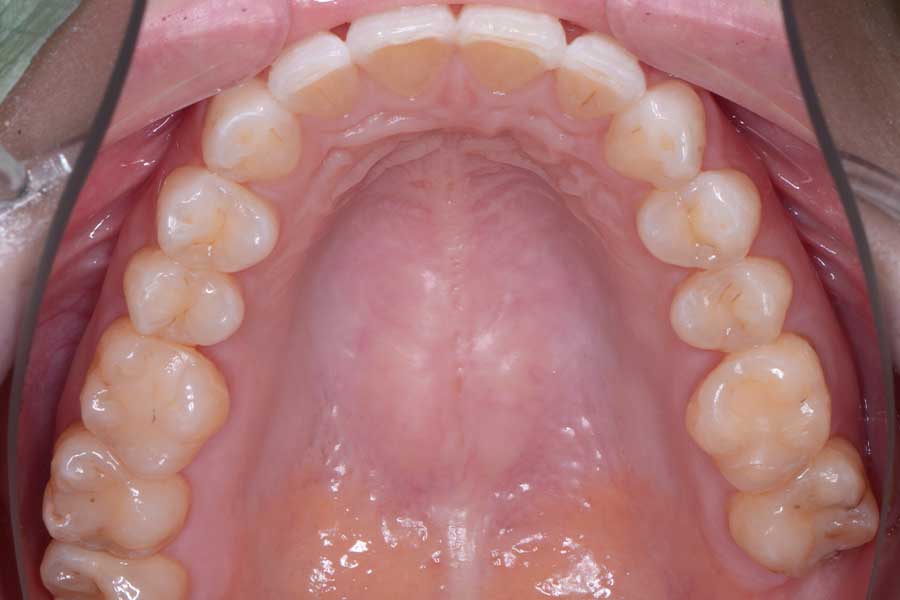

治療後

主訴 インプラント治療前にブラックトライアングルを消したい

治療内容 上下顎ラビアル矯正(表側矯正)